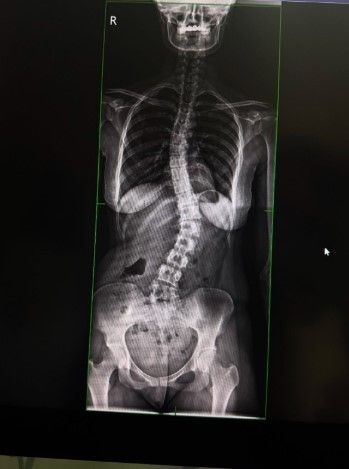

Ish-banorja e Big Brother VIP Kosova, Anisa Veseli, ka ndarë me ndjekësit e saj në Instagram një përvojë shumë të rëndësishme dhe emocionuese: operacionin që ajo ka bërë për skoliozën.

Ajo ka postuar një fotografi nga shtrati i spitalit, ku tregon se ka kaluar me sukses këtë ndërhyrje kirurgjikale të vështirë.